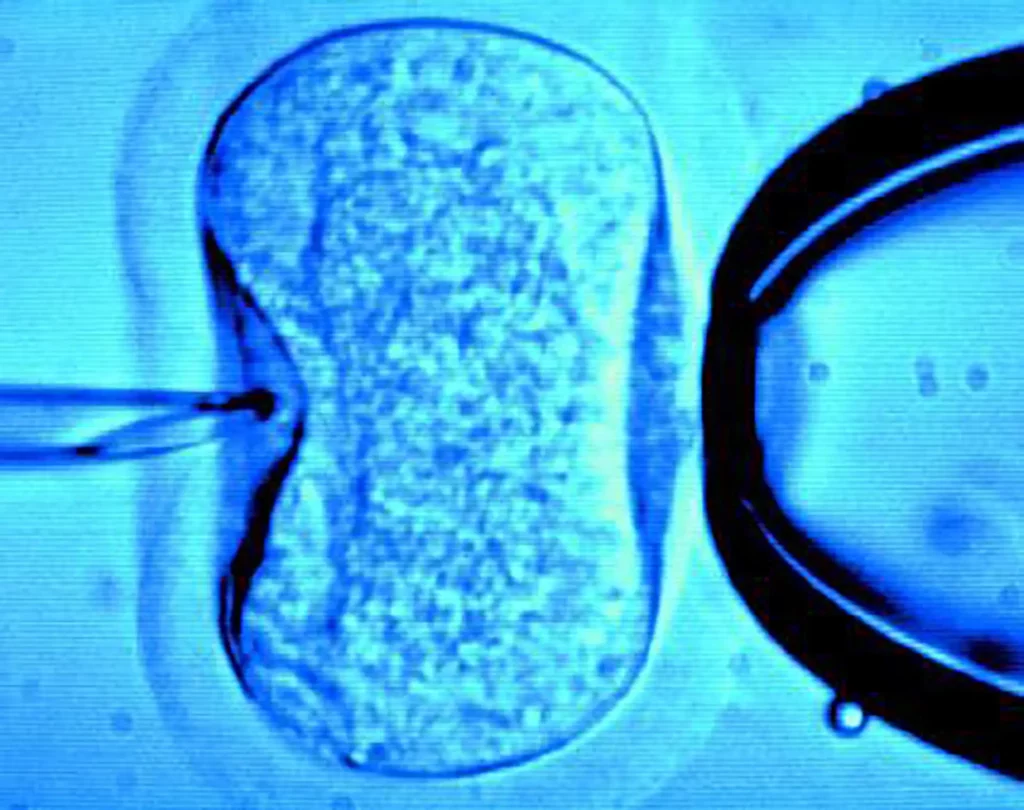

Marie-France Collard : Nous sommes arrivés à un stade de l’évolution de l’humanité où celle-ci s’est créé la possibilité d’œuvrer à sa propre fin. C’est donc, brièvement résumée, l’idée centrale du projet TOVARITCH. Il y a, bien sûr, les armes atomiques qui ont cette capacité. Et rien, dans l’histoire de l’Homo Sapiens, ne permet de penser qu’il sera assez « sapiens » pour ne pas les utiliser. D’autant qu’il a à sa portée, aujourd’hui, les moyens scientifiques pour intervenir sur son identité même. Le volet 2, FRANKENSTEIN – c’est un titre provisoire – traite de la manière dont la science s’est emparée du corps et essaie de le transformer, entre autres, à travers quelque chose d’essentiel, de fondateur pour l’esprit humain, c’est-à-dire : la reproduction, le rapport à l’autre sexe, au désir et le rapport à la descendance. Grâce à la biogénétique, on peut, depuis quelques décennies, enfanter sans avoir eu de rapport sexuel, par fécondation in vitro et réimplantation de l’embryon dans l’utérus. On peut également effectuer des diagnostics pré-implantatoires sur les embryons congelés disponibles, détecter telle ou telle maladie, et pourquoi pas bientôt, le sexe, la couleur des yeux, puis les « trier » et sans doute intervenir sur le code génétique, dans l’idée d’obtenir un enfant considéré comme « parfait » – notion ô combien subjective – tout cela, si les législations le permettent, pris en charge par la médecine. Certains envisagent également l’ectogenèse, c’est-à-dire le fait de conduire une grossesse à son terme complètement à l’extérieur du corps féminin. C’est la porte ouverte à tous les possibles… Enfin, il existe une autre potentialité : dans un futur pas très lointain, en combinant la biotechnologie, la nanotechnologie, la robotique, l’intelligence artificielle, il sera sans doute envisageable de concevoir un être complètement artificiel, bien que fait en partie de matière organique, capable de s’auto-reproduire et qui finalement pourrait donner naissance à une nouvelle « espèce ».